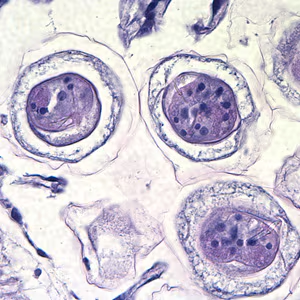

Hymenolepis diminuta eggs in wet mounts.

Hymenolepis nana egg in wet mounts.

Hymenolepis nana eggs, zinc PVA trichrome stain.